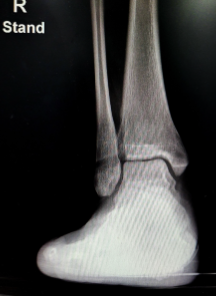

발목 인대파열의 치료방법은 손상의 정도와 개인의 상태에 따라 다르지만, 크게 수술적 치료와 비수술적 치료로 나눌 수 있습니다.

수술적 치료는 인대가 완전히 파열되었거나 보존적 치료로 회복이 어려운 경우에 시행합니다. 수술적 치료는 인대를 재결합하거나 인공인대로 대체하는 방법이 있으며, 수술 후에는 기브스로 고정하고 목발로 보행합니다. 수술적 치료의 회복기간은 약 6주 정도입니다.